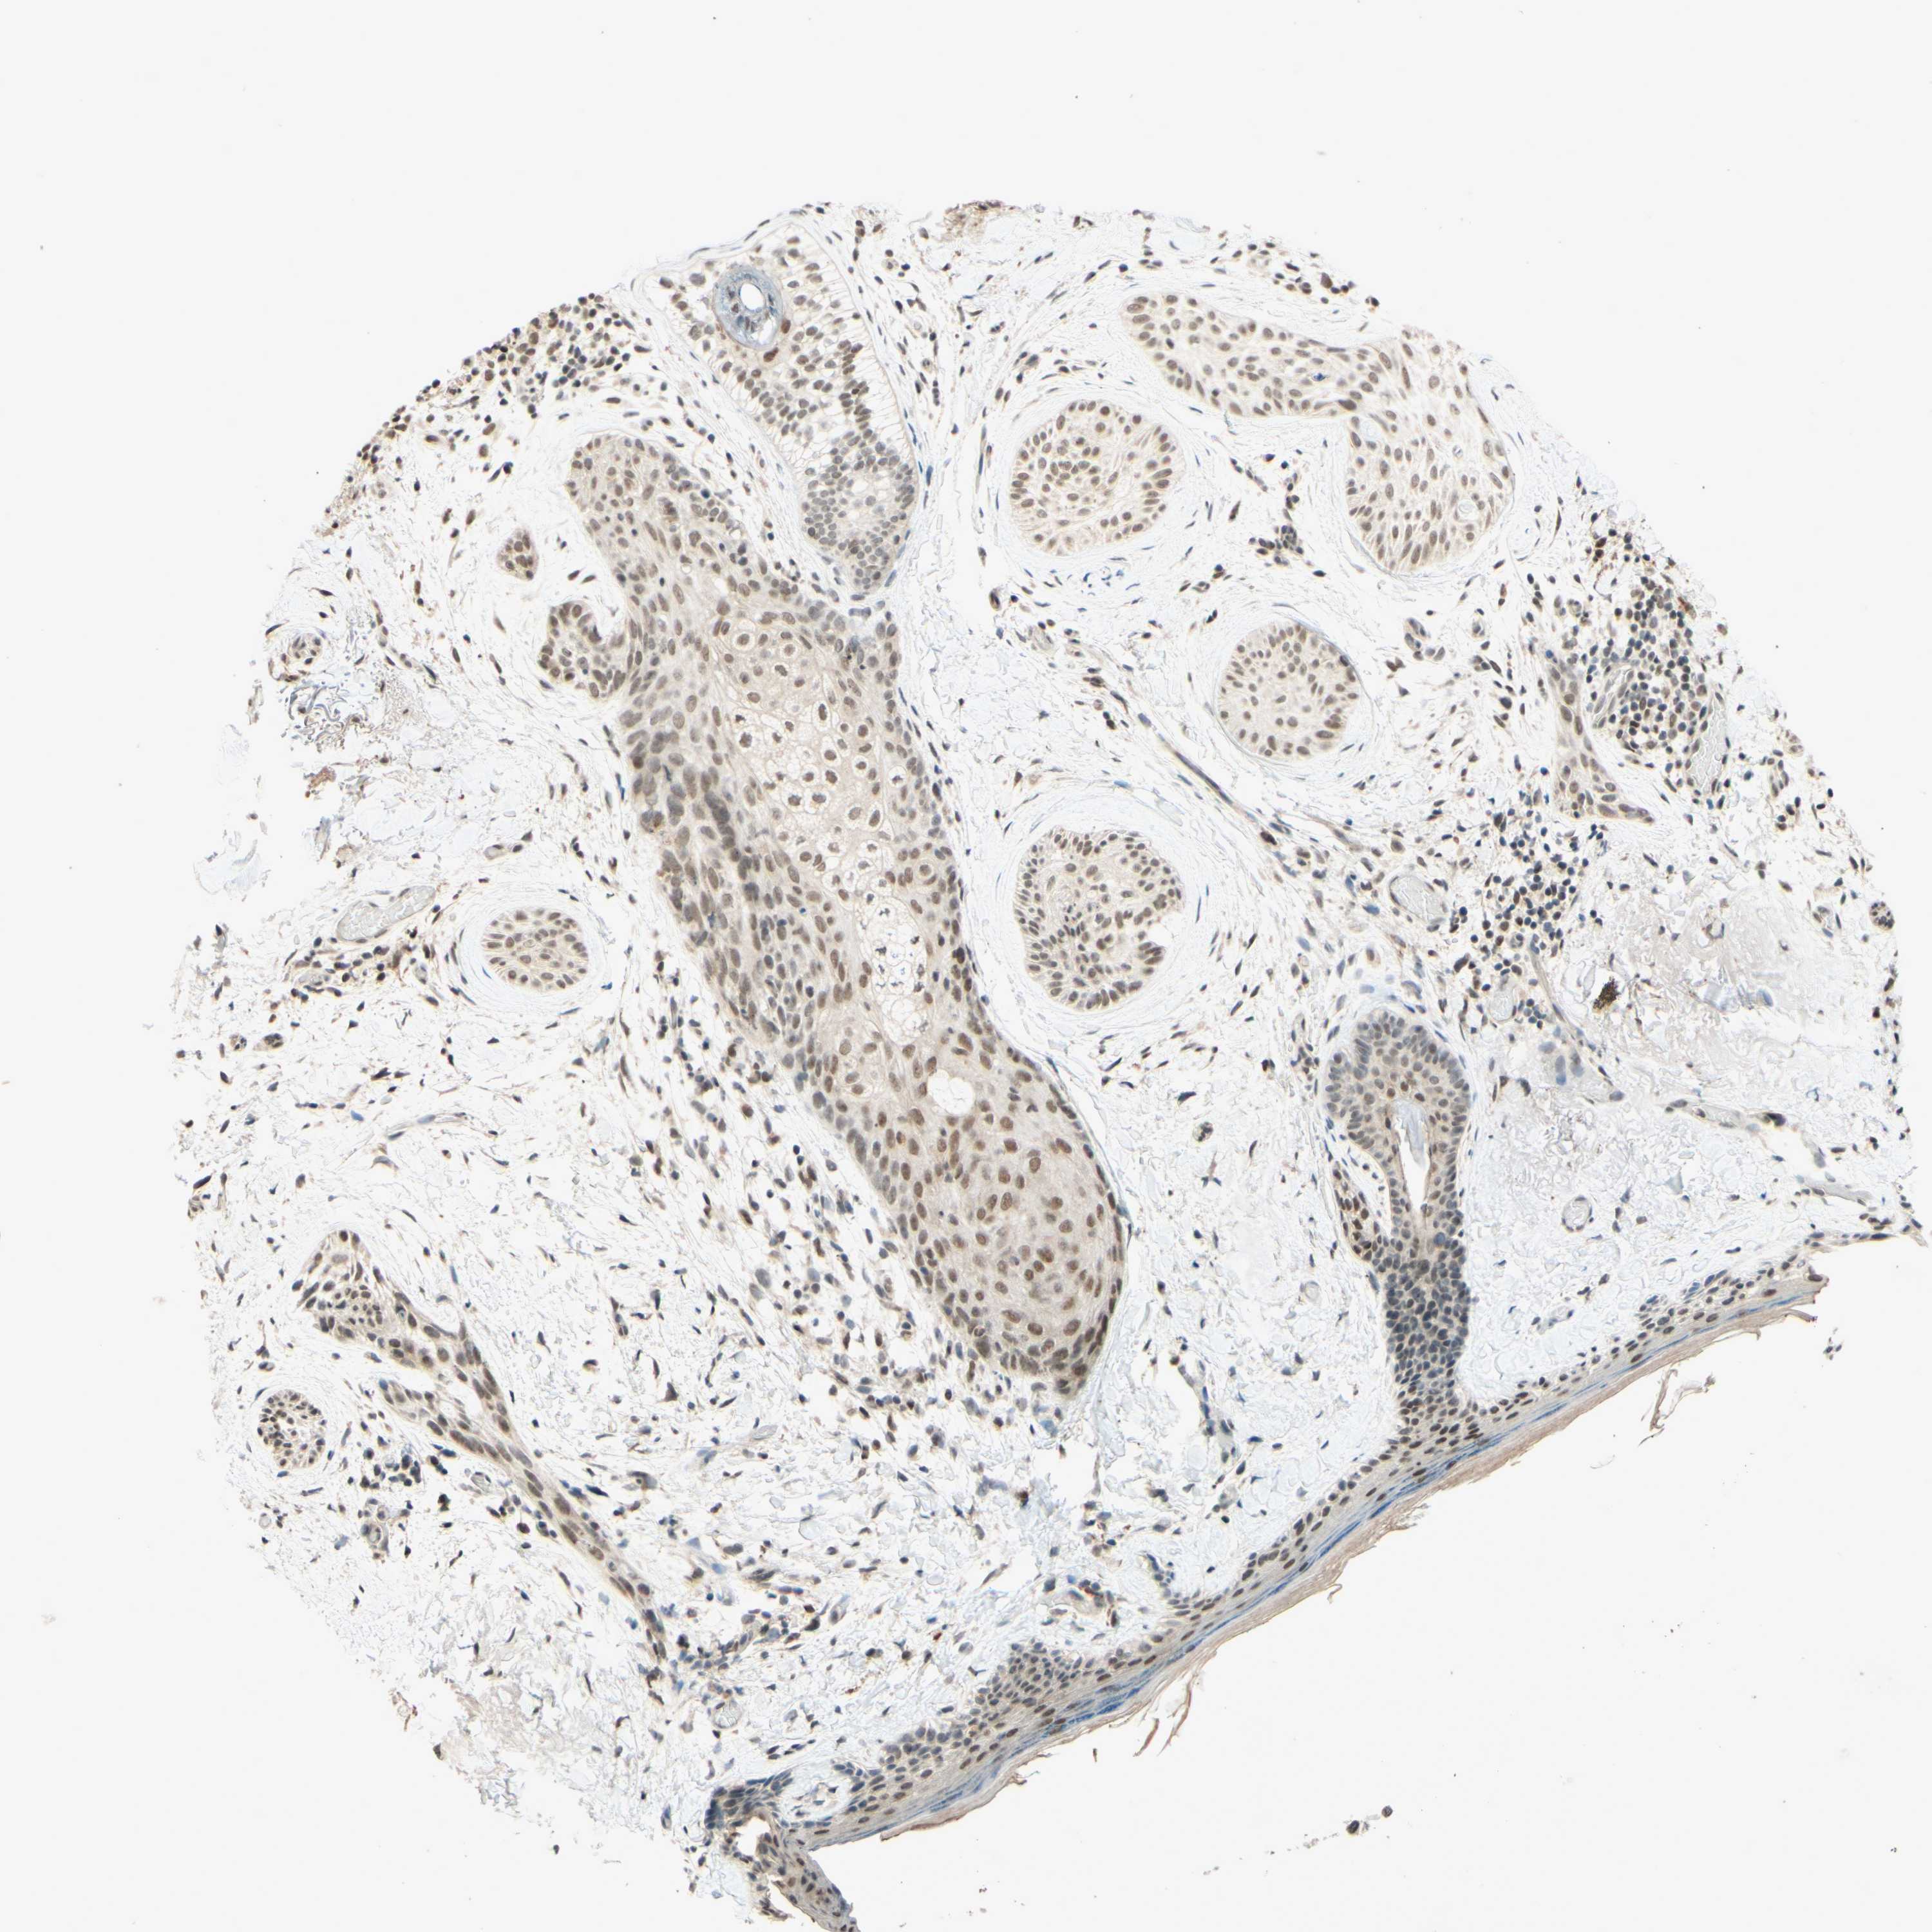

SKIN CANCER - Protein expressioni

A mouse-over function shows sample information and annotation data. Click on an image to view it in a full screen mode. Samples can be filtered based on level of antibody staining by selecting one or several of the following categories: high, medium, low and not detected. The assay and annotation is described here.

Each image is clickable and will lead to virtual microscopy that enables deeper exploration of all samples and also displays staining intensity scores, fraction scores and subcellular localization as well as patient and tissue information for each sample.

Antibody HPA018248

Staining

High

Medium

Low

Not detected

Intensity

Strong

Moderate

Weak

Negative

Quantity

>75%

75%-25%

<25%

None

Location

Nuclear

Cytoplasmic/membranous

Cytoplasmic/membranous,nuclear

Squamous cell carcinoma in situ, NOS